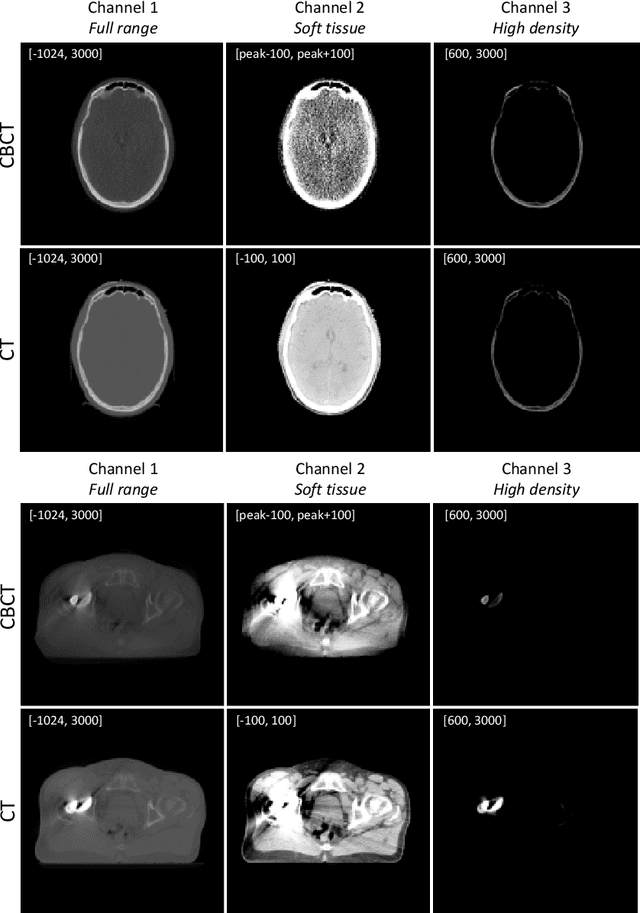

Abstract:Image synthesis is used to generate synthetic CTs (sCTs) from on-treatment cone-beam CTs (CBCTs) with a view to improving image quality and enabling accurate dose computation to facilitate a CBCT-based adaptive radiotherapy workflow. As this area of research gains momentum, developments in sCT generation methods are difficult to compare due to the lack of large public datasets and sizeable variation in training procedures. To compare and assess the latest advancements in sCT generation, the SynthRAD2023 challenge provides a public dataset and evaluation framework for both MR and CBCT to sCT synthesis. Our contribution focuses on the second task, CBCT-to-sCT synthesis. By leveraging a multi-channel input to emphasize specific image features, our approach effectively addresses some of the challenges inherent in CBCT imaging, whilst restoring the contrast necessary for accurate visualisation of patients' anatomy. Additionally, we introduce an auxiliary fusion network to further enhance the fidelity of generated sCT images.